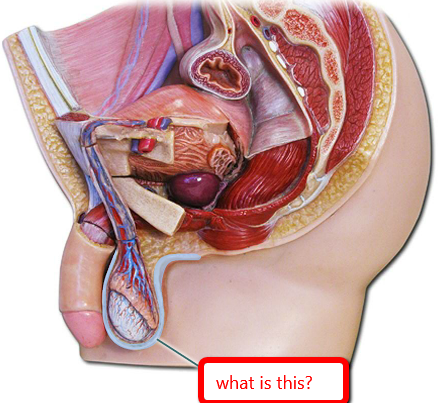

Bulbourethral gland (male)

Bulbourethral gland (female)

Clitoris

External urethral orifice (female)

Labia majora/minora

Vagina

Vaginal orifice

Vestibule (of vulva)